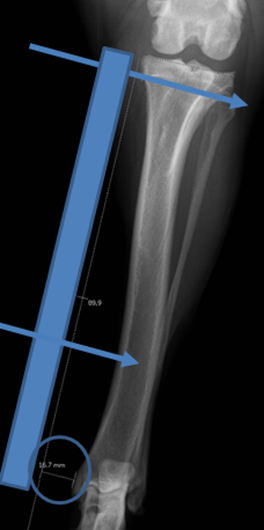

Radiographic Planning: Positioning